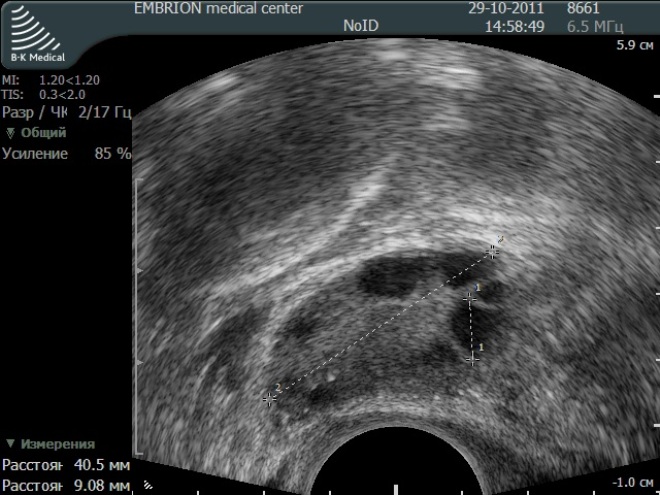

Созревание фолликула в яичнике: этапы и процессы